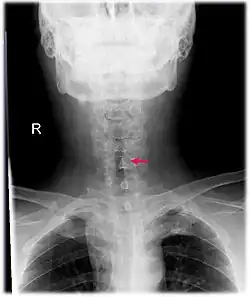

![]() Podgłośniowe zwężenie pointubacyjne na zdjęciu rentgenowskim |

Badania obrazowe

W obrazowaniu krtani stosuje się tomografię komputerową, czasem także rezonans magnetyczny. W przypadkach wrodzonego porażenia fałdów głosowych konieczne jest wykonanie rezonansu magnetycznego głowy w celu wykluczenia wad ośrodkowego układu nerwowego. Zdjęcia rentgenowskie, ze względu na nakładające się cienie tkanek miękkich i kości, mają mniejszą wartość diagnostyczną[108][23].